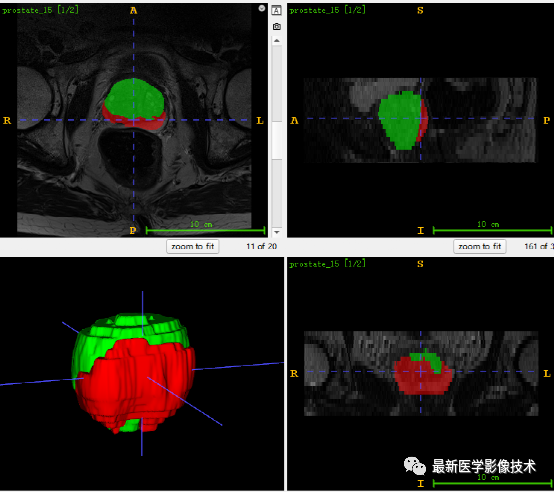

6、测试集分割结果